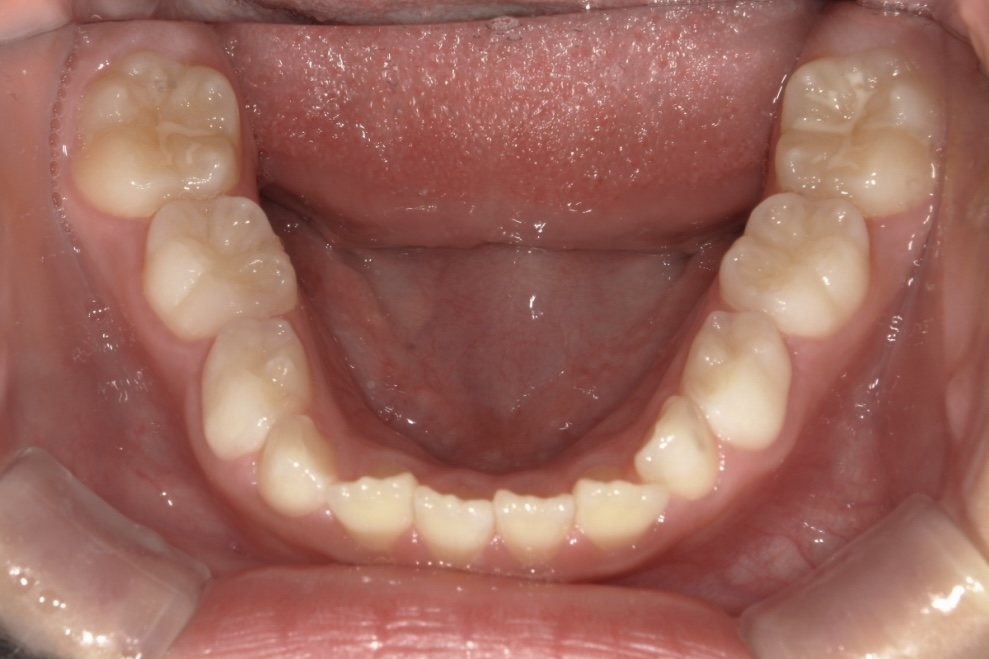

BEFORE

9歳男児 すきっ歯とガタガタが気になる

主訴は歯並びのガタつきとすきっ歯でした。できるだけ痛みや不快感の少ない方法で治療を進めたいとのご希望をお持ちでした。